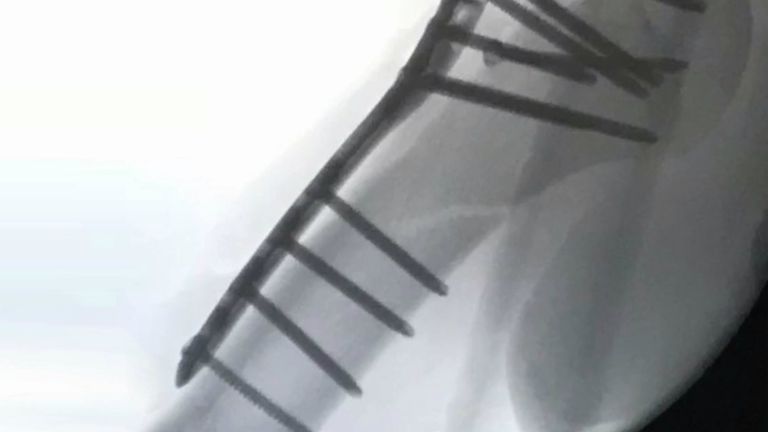

Sterker nog, Niek heeft de training al hervat op het sportcomplex van NOC*NSF in Papendal, bij Arnhem. Met tientallen schroeven en een plaatje in zijn arm, dat dan weer wel. “Mijn arm is nog wat stijf, maar het gaat bijzonder goed.”